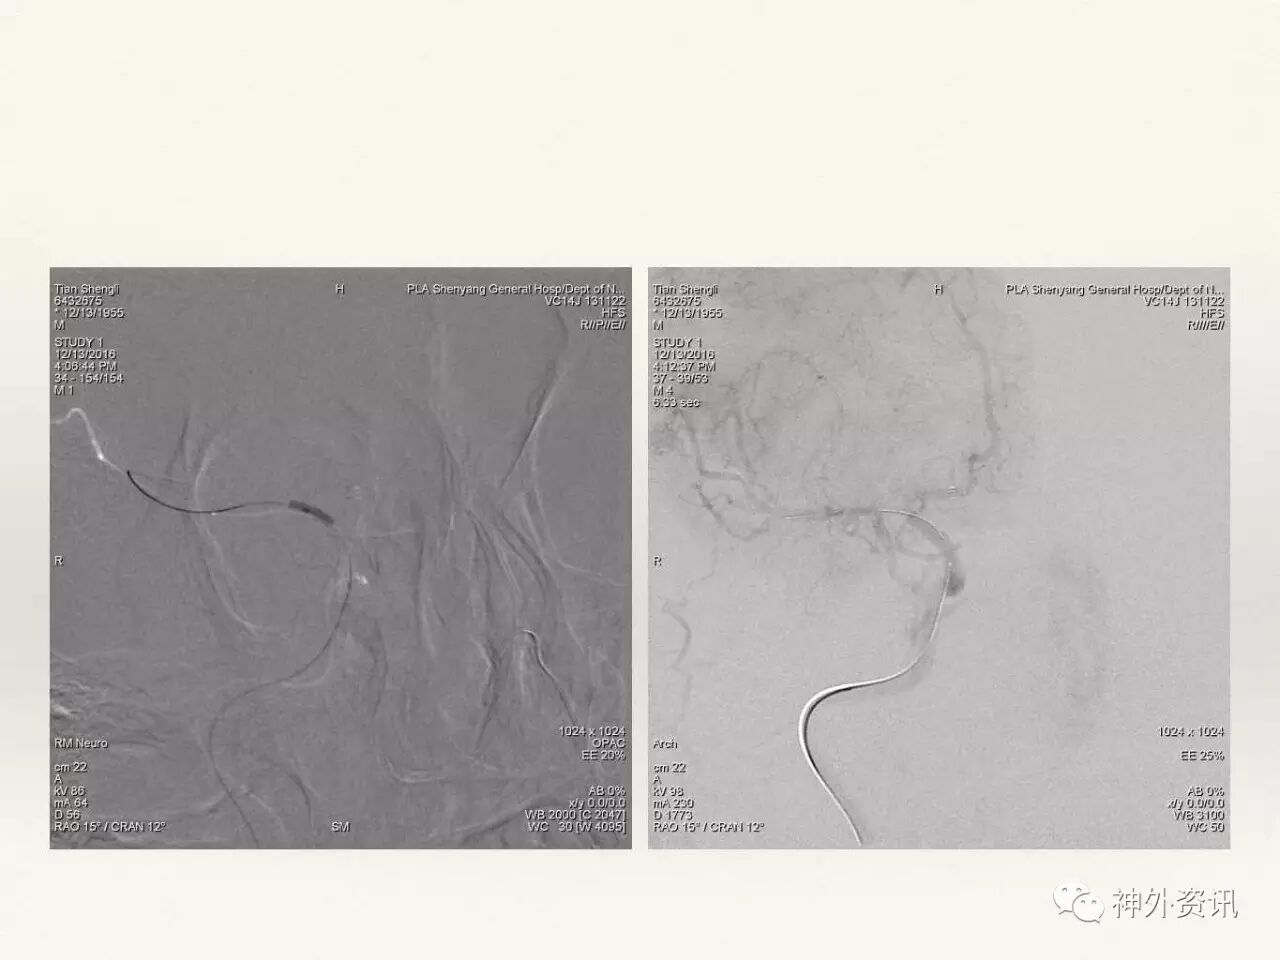

在东北地区率先开展了颈内动脉、大脑中动脉及基底动脉闭塞血管内再通、颅内动脉栓塞急性期取栓、血流导向装置治疗大型宽颈动脉瘤等,对颅内动脉瘤、动静脉畸形、颈动脉及颅内动脉狭窄、颈内动脉海绵窦瘘、硬脑膜动静脉瘘等外科治疗具有较深的造诣。完成脑血管造影8600余例,各类脑血管病介入手术共4500余例,动脉瘤、动静脉畸形、脑肿瘤、脑出血及脑外伤等外科手术1500余例。